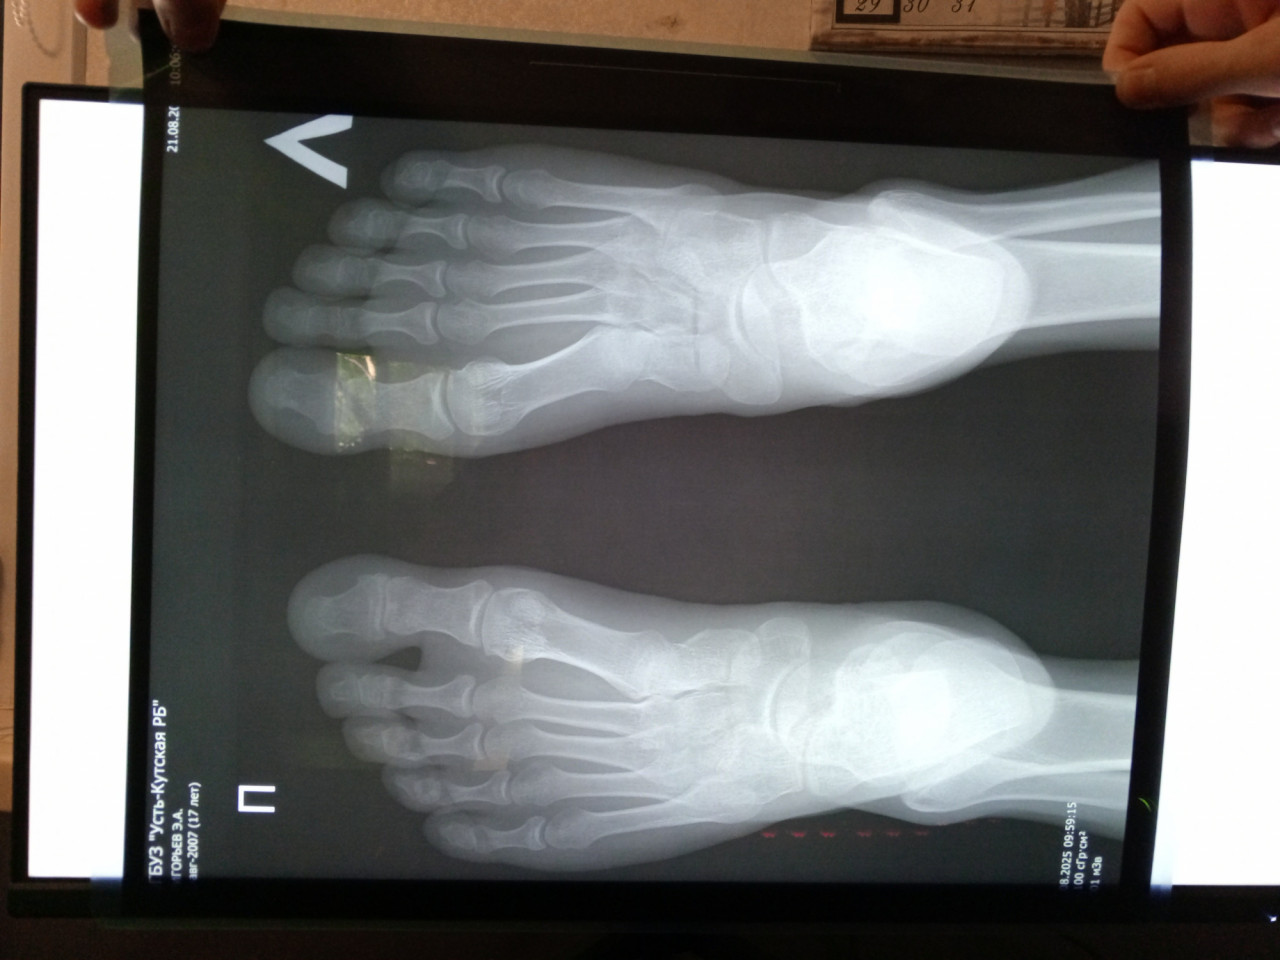

Здравствуйте. Сыну 17 лет. Были на приёме у ортопеда. Заключение после осмотра: эквино-плоско-вальгусная деформация стоп. Сделали рентген в двух проекциях: прямой без нагрузки и боковой с нагрузкой. В заключении написано плоскостопие 1ст. А про вальгус ничего. Из жалоб боли при ходьбе в области пяток в основном. Походка пружинящая, пятками еле касается пола. Посмотрите пожалуйста снимки, действительно у него плосковальгусная стопа? Или же нужно искать причину болей в другом?

Здравствуйте. По рентгену у вашего сына действительно отмечаются признаки плоскостопия 1 степени. Вальгусная деформация выражена слабо, поэтому в заключении её могли не указать. Боли в пятках и пружинящая походка могут быть связаны не только с плосковальгусной стопой, но и с перегрузкой ахиллова сухожилия или проблемами с пяткой. Рекомендую повторно показать ребёнка ортопеду, сделать УЗИ мягких тканей стопы и при необходимости дообследование, а также использовать индивидуальные ортопедические стельки.

Здравствуйте.  На снимках видно уплощение сводов стоп, что подтверждает плоскостопие начальной степени. Чёткой выраженной вальгусной деформации не прослеживается, поэтому в заключении её могли не отметить. Однако жалобы на боли в пятках требуют дообследования и стоит исключить воспаление подошвенной фасции или перегрузку зоны роста пяточной кости. Рекомендую обратиться к ортопеду для подбора ортопедической обуви или стелек, ограничить длительные нагрузки и по показаниям пройти физиотерапию.